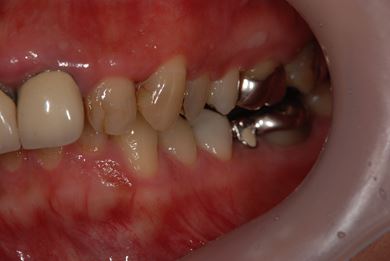

| 性別/年齢 | 女性 / 41歳 | ||||||||||||||||||||||||||||||||

| 主訴 | 歯が欠けたので、セラミック治療をお願いしたい。 | ||||||||||||||||||||||||||||||||

| 治療方針 | セラミック治療にて、審美的回復を行う。 | ||||||||||||||||||||||||||||||||

| 治療内容 | エンプレスオールセラミッククラウン4本(オールセラミック用土台4本) | ||||||||||||||||||||||||||||||||

| 総治療費 | 408,000円 | ||||||||||||||||||||||||||||||||

| 治療期間 | 4ヶ月 |